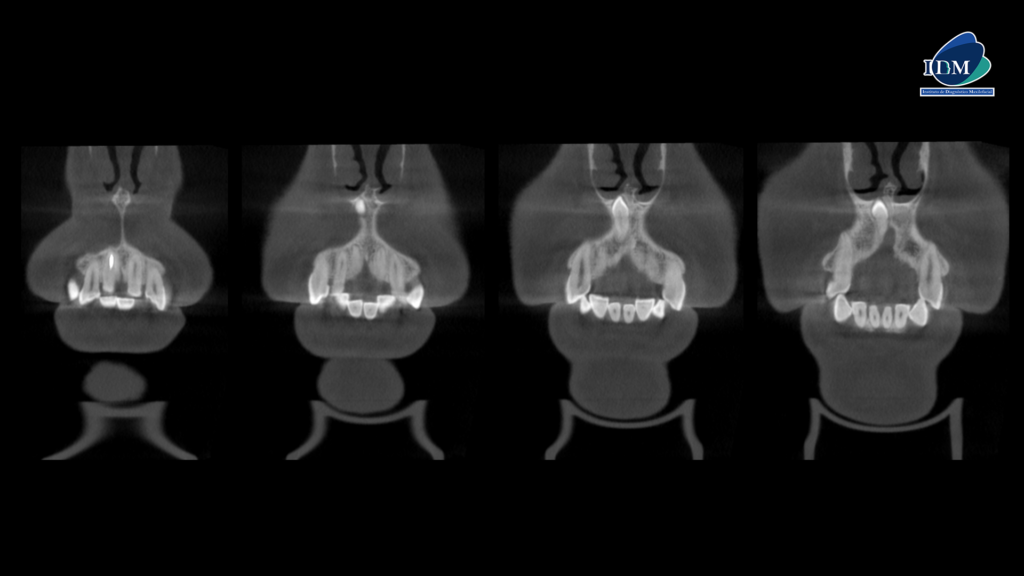

A la evaluación de la radiografía panorámica se evidencia un diente supernumerario retenido en posición invertida en sector anterosuperior.

Radiografia Panorámica

CORTES CORONALES